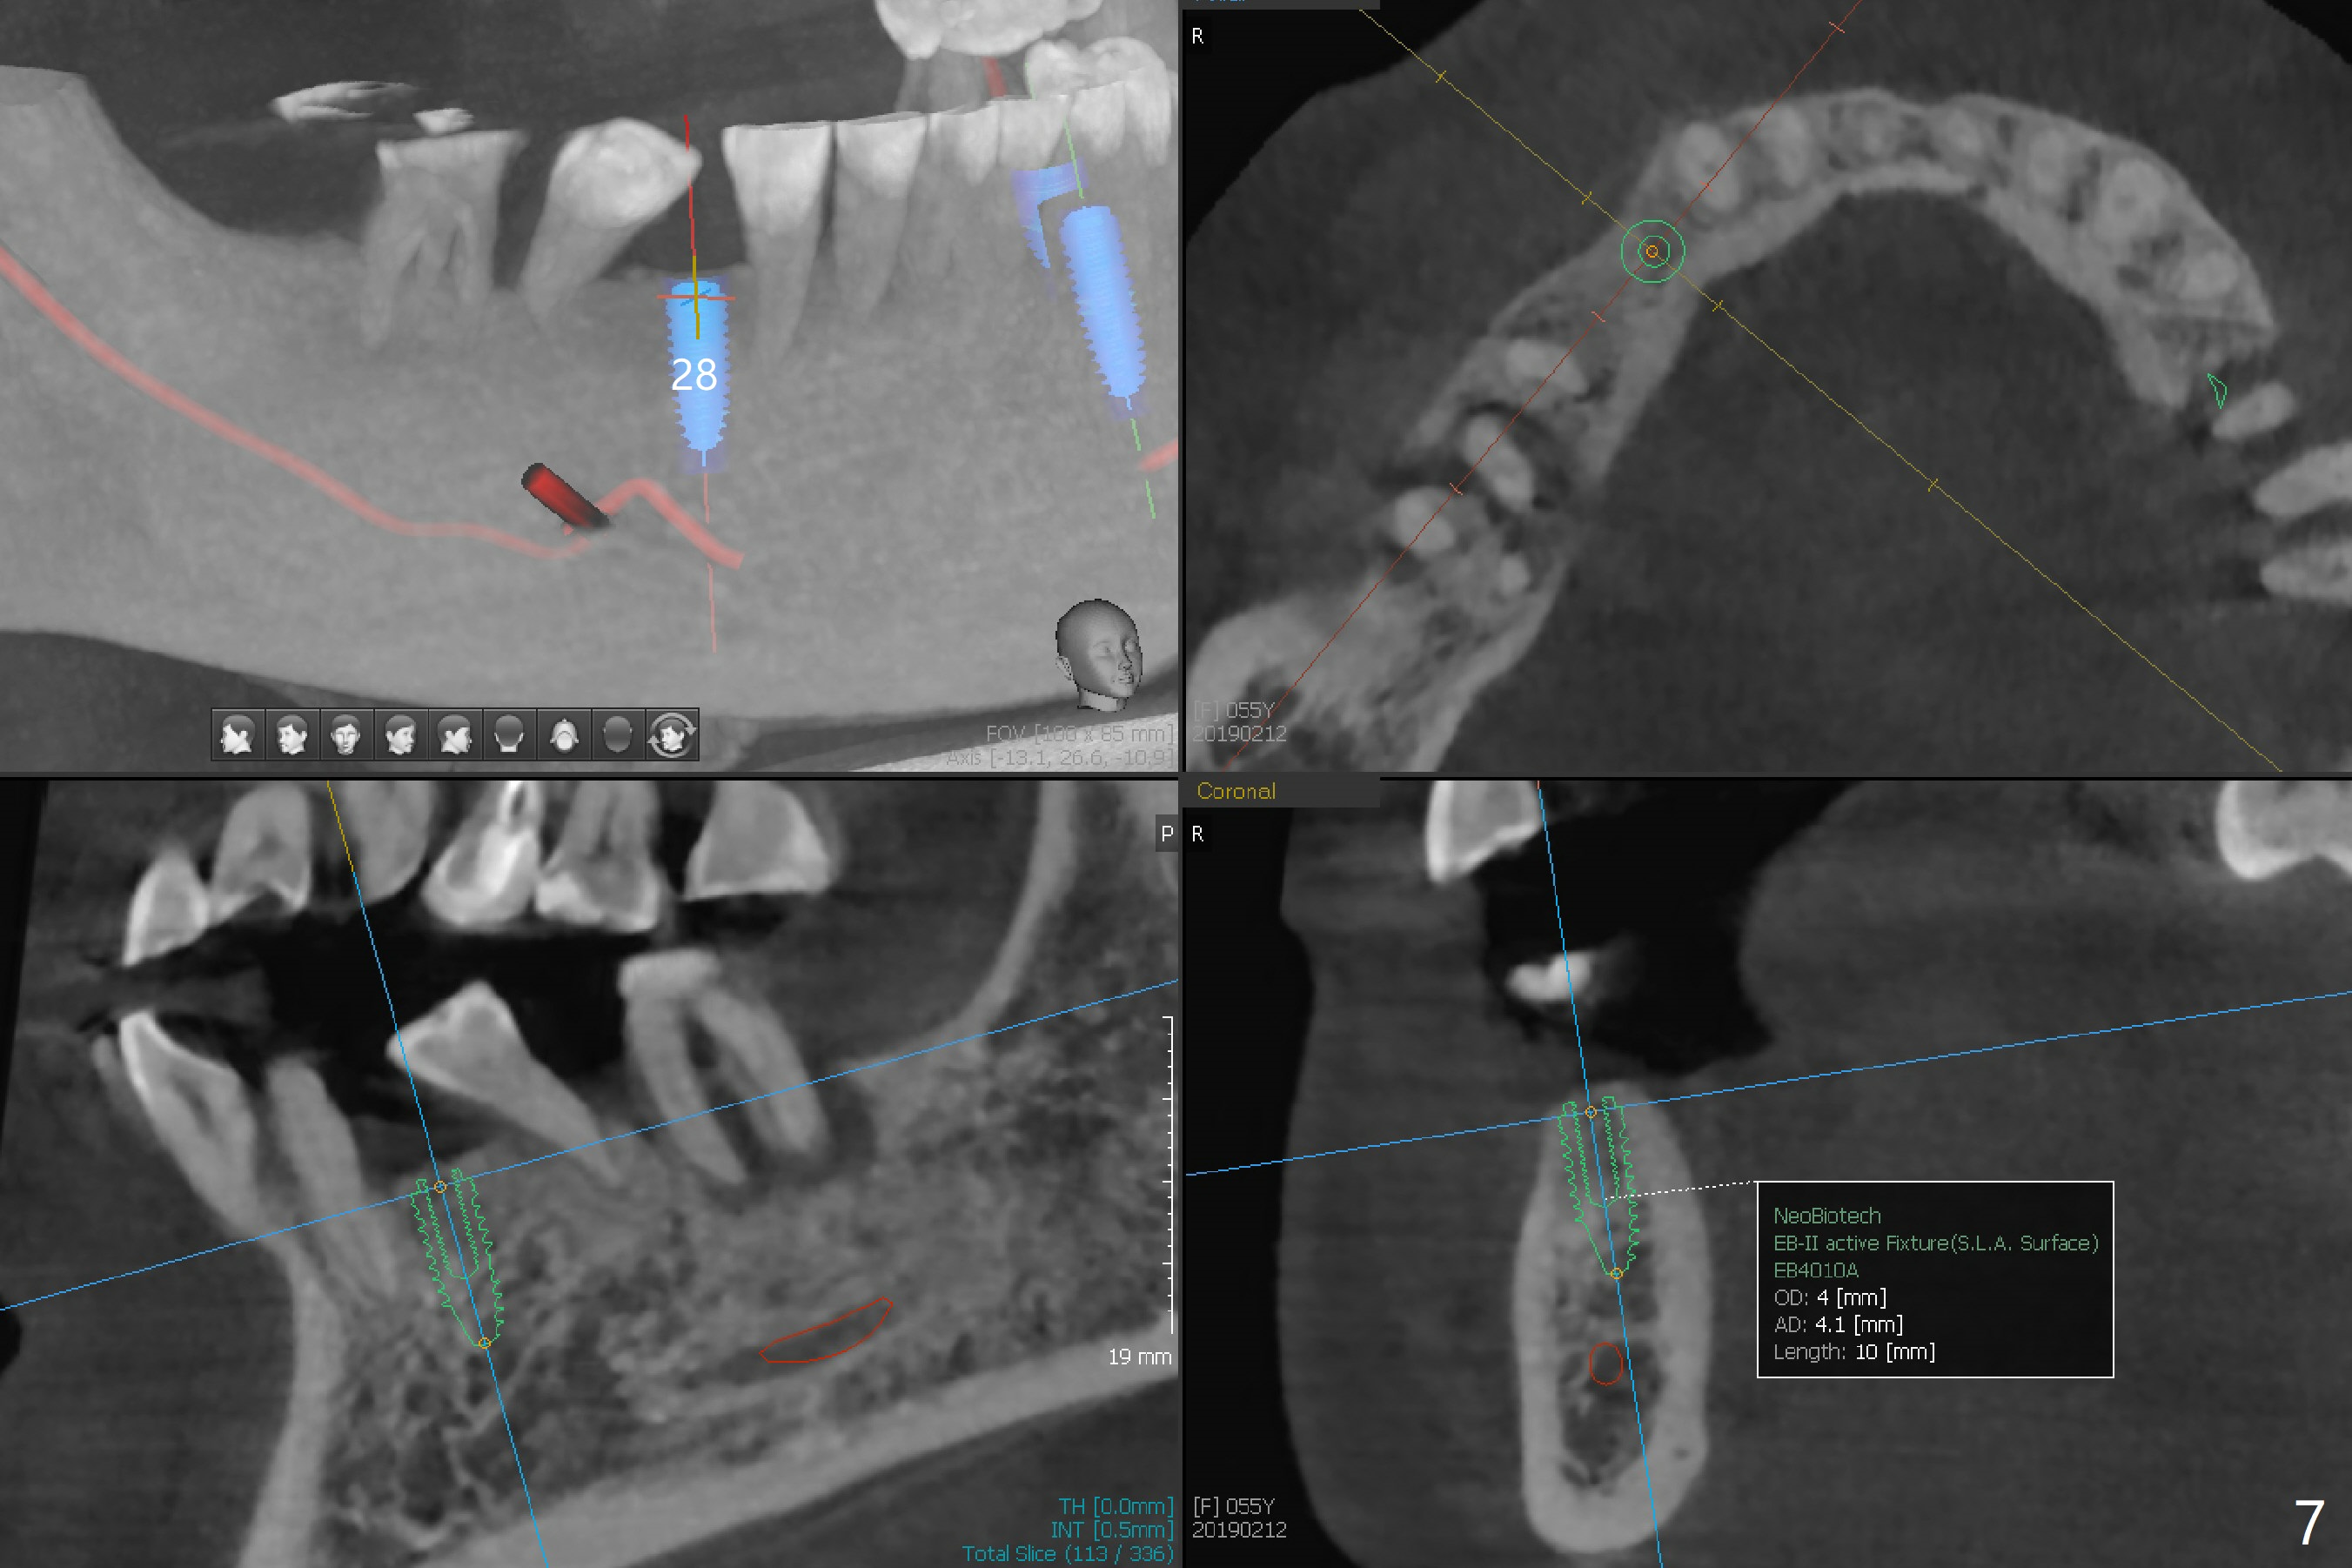

A 55-year-old woman has poor dentition, which is partially related to her previous history of ice chewing (Fig.1). The long bone height in the jaws suggests bruxism and requires as many teeth and implants as possible. After SRP, caries will be removed from #14 and 15 for determination of salvageability (Fig.2). The patient prefers to save the tooth #30. Endo referral will be recommended for #14 and 30. If the tooth #14 proves to be nonsalavageable, it will be extracted with #12 for immediate implants and subsequent FPD (Fig.3,4). Immediate implant will be avoided at #19 due to severe bone loss. Instead a short implant (5.5x5 or 6 mm) will be placed at #18, while a 4x11.5 mm one at #20 for FPD (Fig.5,6). All of the implant will use guides. There is a special point at #18. After use of 4.5 mm drill, the guide will be removed for free hand osteotomy using 5.0 mm drill, 5.5 mm tap and implant placement. PRF will be prepared for membrane and sticky bone at #19 and 20. For the lower right quadrant, treatment for #30 should be conducted first, either RCT or implant. The tooth #29 will be uprighted using #30 as an anchor, if the former is salvageable. The implant at #28 will be placed last (Fig.7,8).